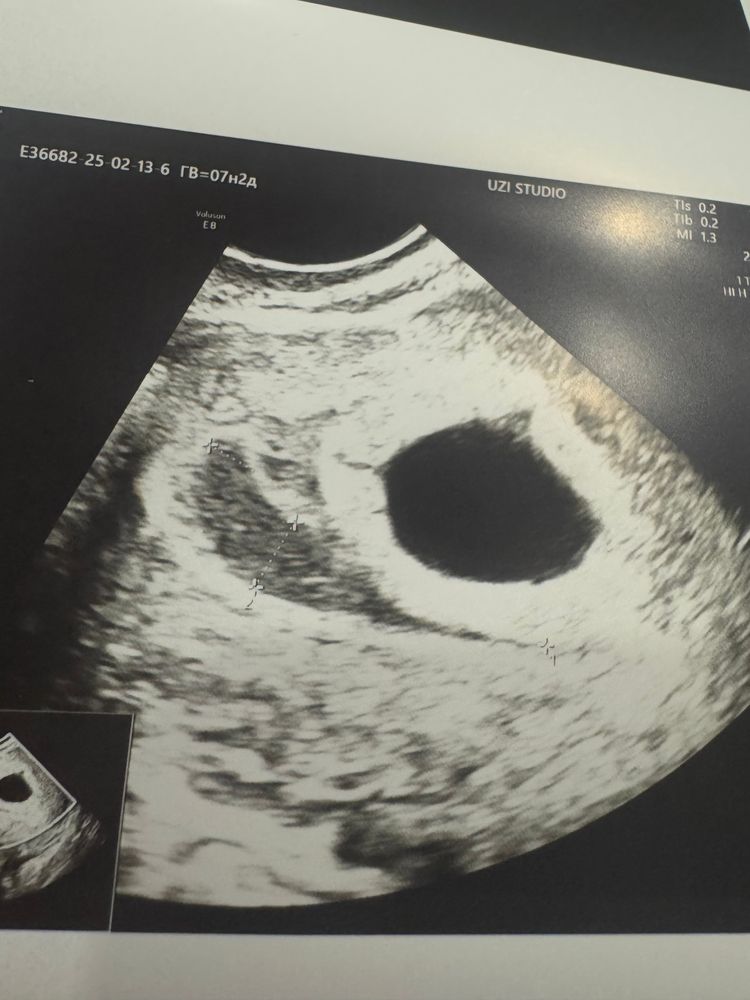

Нашли гематому на узи, посмотрите кто разбирается

А у вас СБ определили сегодня на узи ? Я не пойму , но похоже на пустое плодное яйцо

Алена, да, 129 ударов, это смотрели датчиком через живот, эмбрион в плодном яйце все что хорошо с ним)